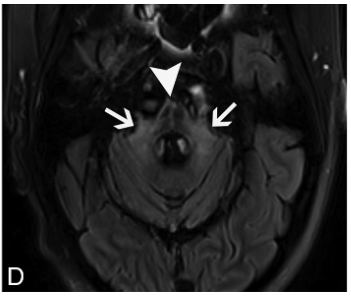

画像所見は,病期によって画像所見が異なる.

急性期は小脳や小脳脚,脳幹部のT2高信号and/or造影効果を呈する.

進行すると(慢性期),小脳や脳幹部が萎縮することがある.Waller変性を生じると橋の十字型T2高信号や中小脳脚のT2高信号を生じ,多系統萎縮症(MSA)と非常に類似した画像となりうる.

オリーブ核の異常肥大性変性(Hypertrophic olivary degeneration)が見られることがあり,歯状核ルイ体オリーブ経路が障害されるためと考えられる.